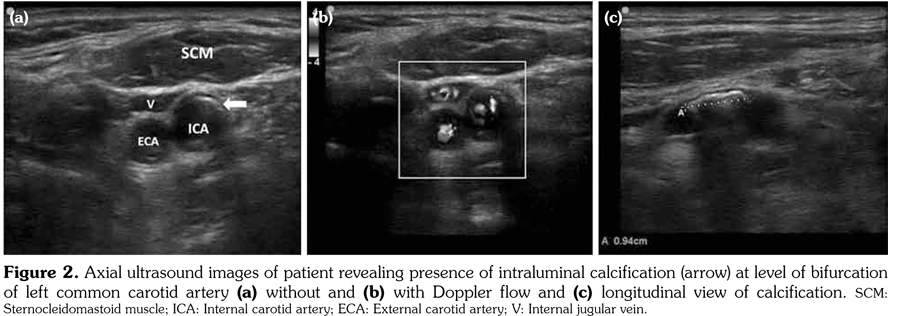

An 80-year-old female patient was examined due to complaint of neck pain over the last year which has aggravated recently. She denied history of trauma. Her medical history indicated that she was taking some medications for hypertension and coronary artery disease. Physical examination was compatible with cervical osteoarthritis with limited cervical range of motion in all directions and tenderness to palpation. Laboratory findings including complete blood count, erythrocyte sedimentation rate, C-reactive protein, serum calcium, phosphorus, parathyroid hormone, and vitamin D levels were within normal ranges. On radiological evaluation, cervical X-ray revealed a calcified mass in the left mid-paravertebral region with cervical degenerative changes (Figure 1). At first glance, a calcification inside the cervical muscles was suspected. Ultrasonographic examination of the cervical region revealed the presence of intraluminal calcification at the level of the bifurcation of the left common carotid artery (Figure 2a-c). The patient was referred to neurology department for being at risk for stroke.

Carotid arteries are the major vascular structures that deliver blood to brain. A blockage in carotid arteries can lead to stroke which is typically caused by atherosclerosis.(1) The artery-wall thickens as a result of invasion and deposit of white blood cells and proliferation of intimalsmooth-muscle cell creating a fatty plaque which is known as atherosclerosis.(2) These deposits also contain cellular waste, cholesterol, and triglycerides with often occurring calcification.(2) Therefore, paravertebral calcifications seen on X-ray might be inside the vessels, particularly in the elderly. Complications of the carotid artery calcification should be kept in mind, so that the patient can be referred to the relevant departments before occurrence of catastrophic consequences such as stroke. Ultrasonography should be the method of choice in confirming the diagnosis.(3)